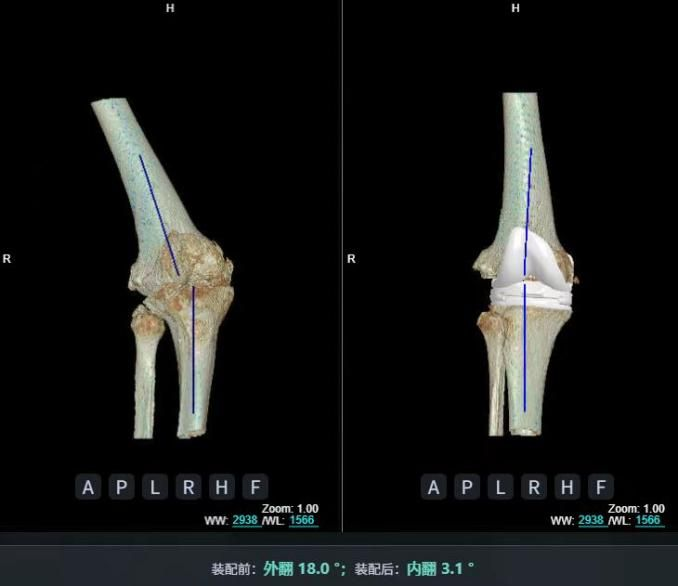

AI精準關節置換治療骨關節炎是指利用人工智能(AI)技術輔助完成關節置換手術,通過術前精準規劃、術中精準操作和術后個性化管理,提升手術效果并優化患者康復。

例如,2025年7月28日,南方醫科大學第三附屬醫院便運用該技術,成功為一位73歲、患有雙膝嚴重骨關節炎伴膝內外翻畸形(“XO 型腿”)的患者完成治療。[11]

術后,患者雙側關節活動度恢復至0-120°,步態基本正常,已重獲行走能力,日常生活質量顯著改善。目前,患者正進行最后的肌力強化訓練,預計三個月后可完全恢復日常活動。